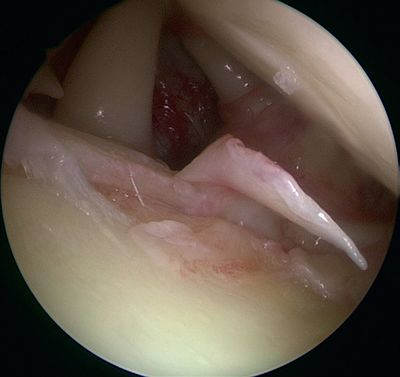

In 1985, Andrews et al. were the first to see, under arthroscopy, superior labral tears (Figure and Video) in 36 throwing athletes (sometimes associated with articular rotator cuff tears).[5]

Articular rotator cuff tears

They reported that simple debridement allowed 85% of athletes to resume their sport at the same level (Figure and Video).

Simple labral debridement